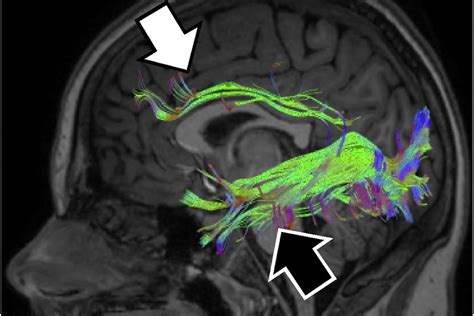

Cortical Vision Impairment (CVI) is a complex condition that affects the brain's ability to process visual information. Unlike traditional eye diseases that impact the eyes themselves, CVI results from damage to the visual cortex or the pathways that connect the eyes to the brain. This condition can significantly impact an individual's ability to perceive and interpret visual stimuli, leading to a range of challenges in daily life. Understanding CVI, its causes, symptoms, and management strategies is crucial for providing effective support and improving the quality of life for those affected.

Cortical Vision Impairment is a neurological condition that arises from damage to the visual cortex or the neural pathways that transmit visual information from the eyes to the brain. This damage can occur due to various factors, including:

CVI can affect individuals of all ages, but it is particularly prevalent in children who have experienced perinatal brain injuries or developmental disorders. The condition can manifest in different ways, depending on the extent and location of the brain damage.

It is crucial to differentiate CVI from other visual impairments, as the management strategies can vary significantly. Early and accurate diagnosis is essential for developing an effective treatment plan and providing appropriate support.